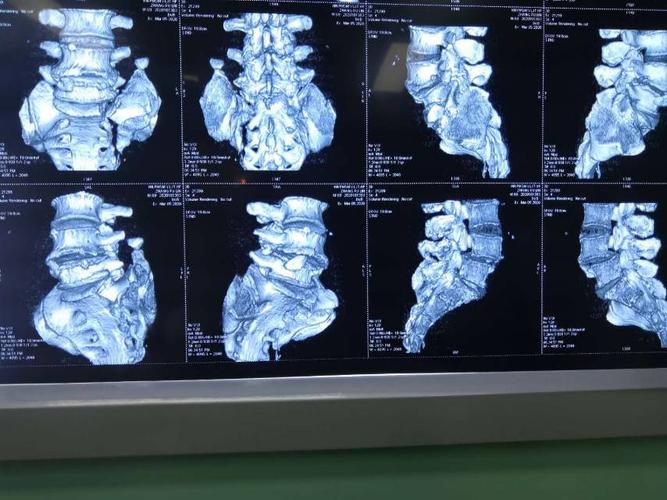

华亭市二院成功开展骨盆骨折伴骶骨骨折手术一例

骶骨骨折会诊,分型?手术方案?固定方式?急诊手术还是择期?

术前骶骨骨折

骶骨翼骨折图片

骶骨骨折图片

骶骨翼骨折

骶骨骨折影像图片